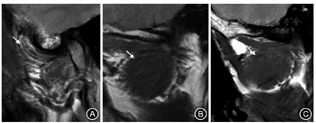

(1)髁突位置分类:根据髁突前、后斜面与关节窝前、后斜面切线间的距离大小可分为前位、后位及中立位(图6)。

(2)髁突形态分类:TMD患者的髁突形态分为卵圆形、扁平形、鸟嘴形(图7)[3];健康人群髁突形态存在个体差异,但髁突形态的变化,尤其是鸟嘴形髁突与关节盘前移有一定关系[1]。